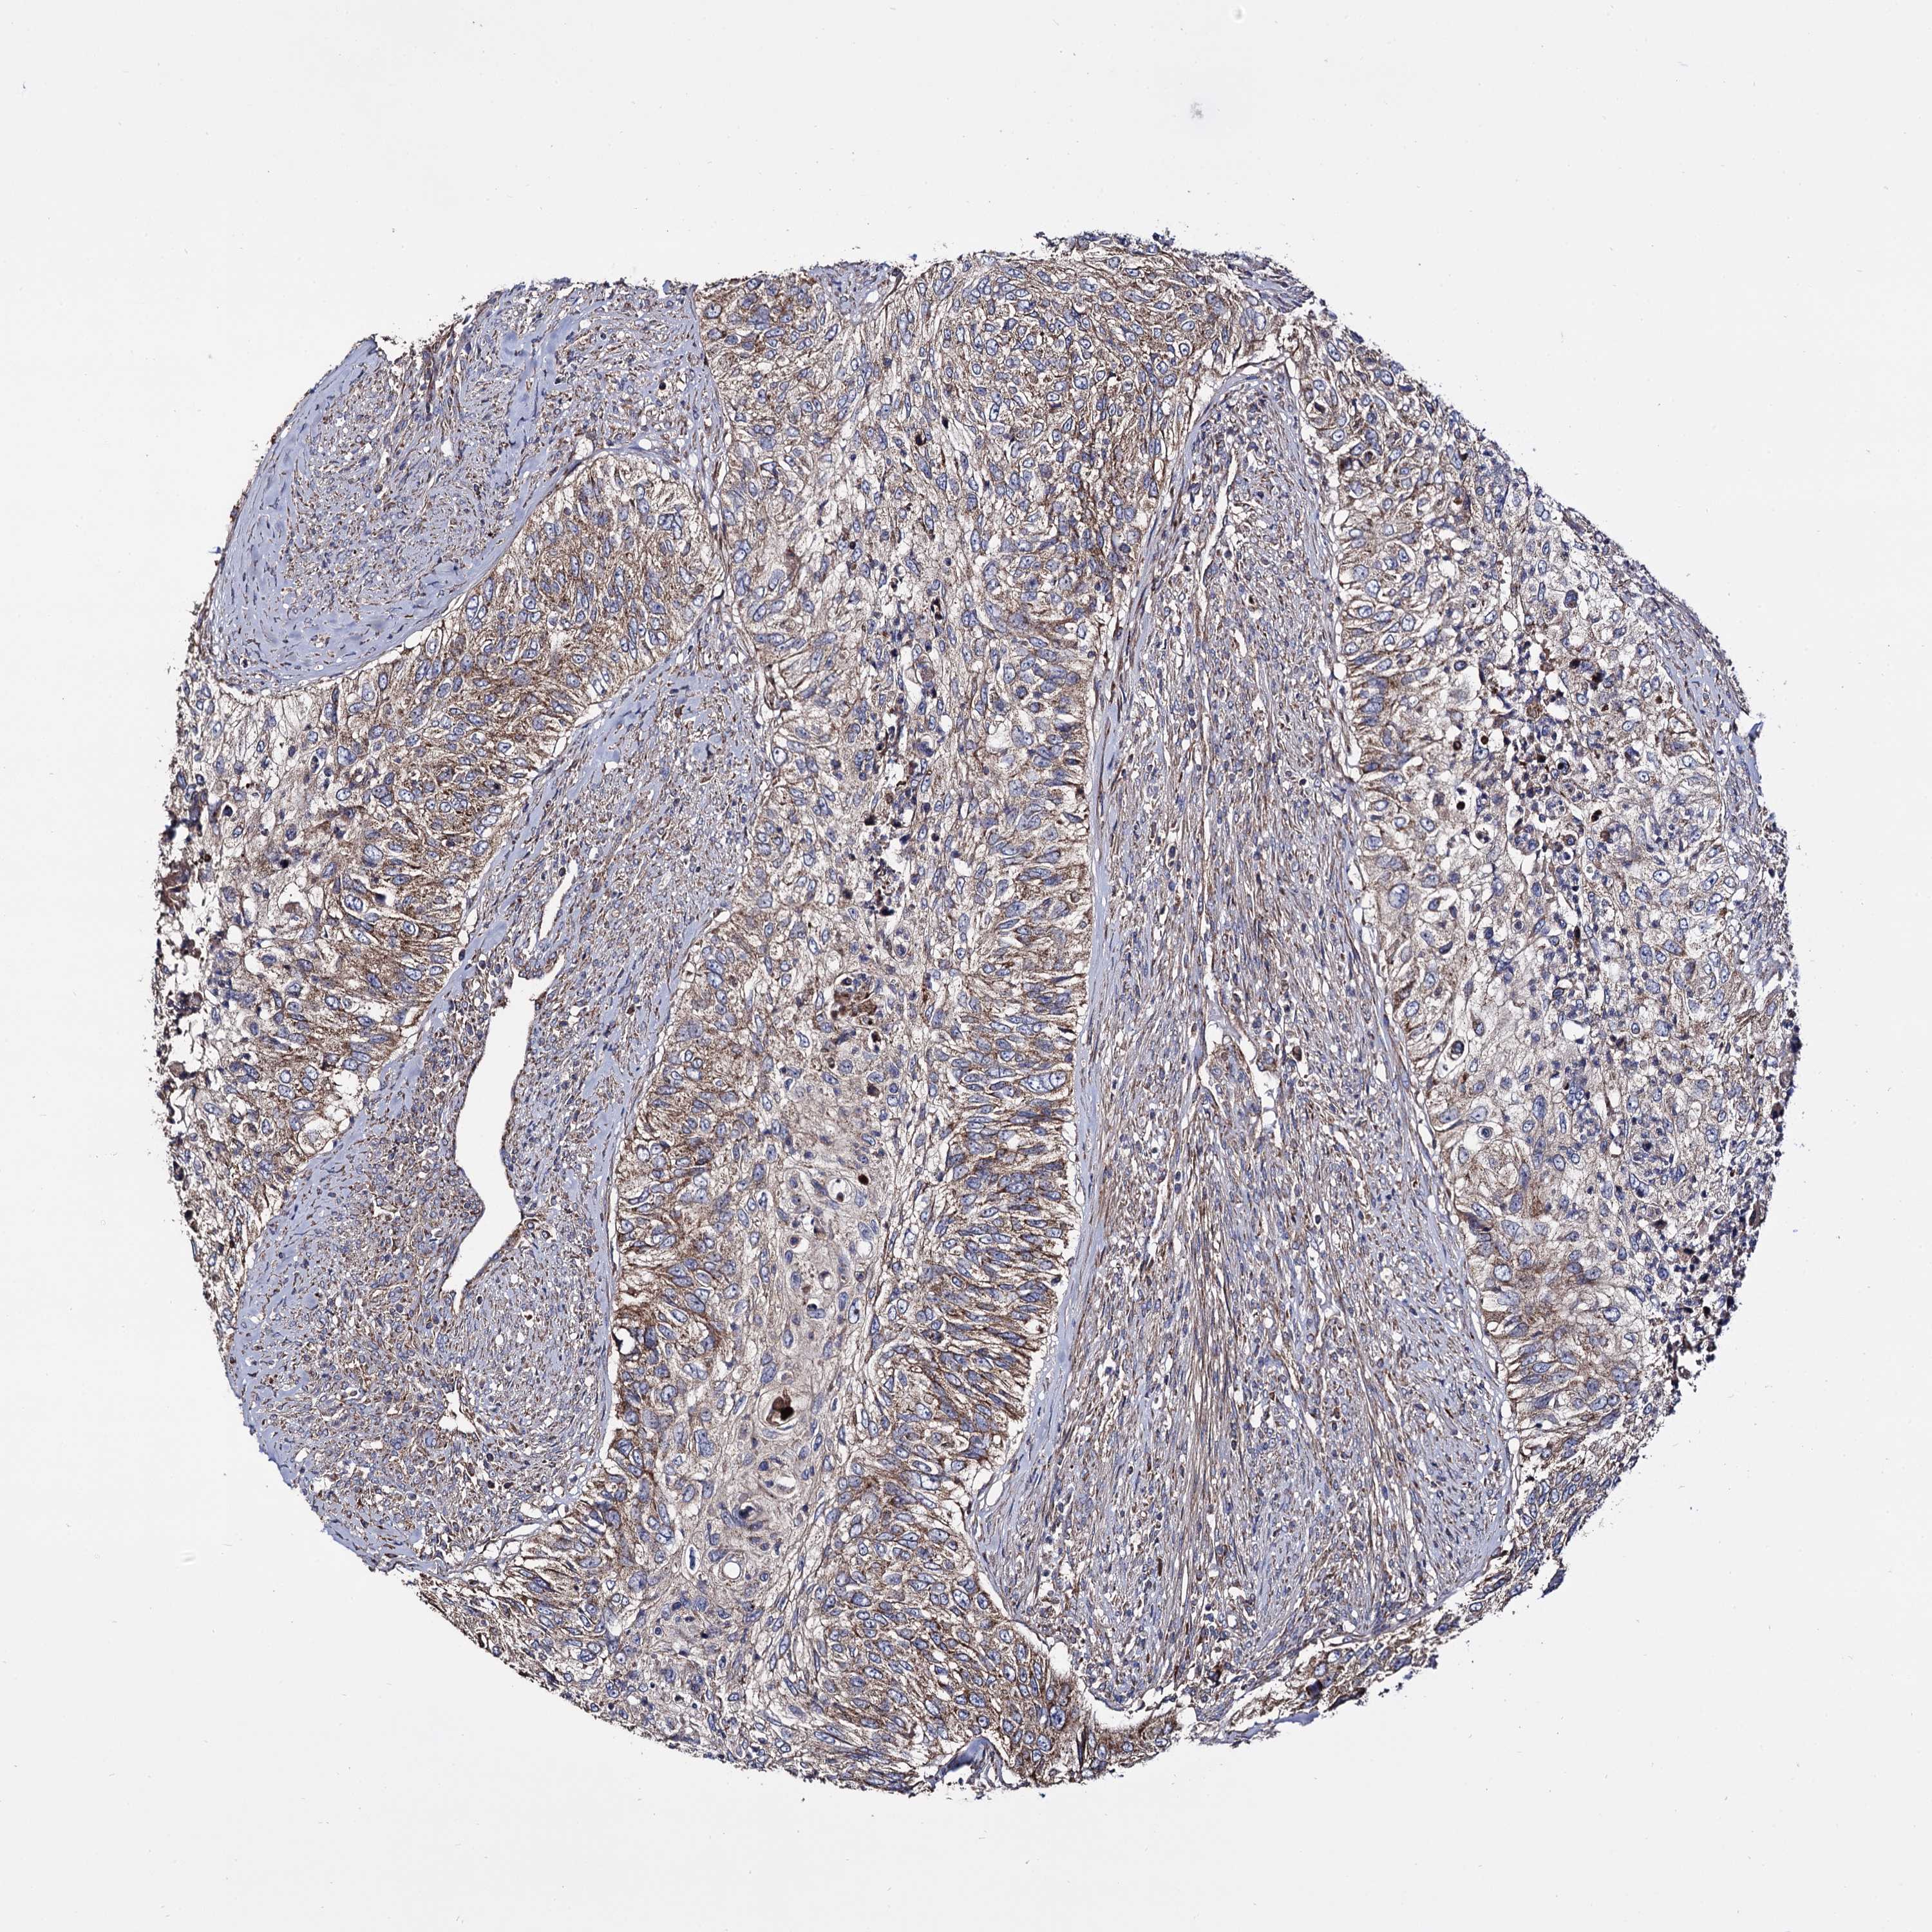

UROTHELIAL CANCER - Protein expressioni

A mouse-over function shows sample information and annotation data. Click on an image to view it in a full screen mode. Samples can be filtered based on level of antibody staining by selecting one or several of the following categories: high, medium, low and not detected. The assay and annotation is described here.

Note that samples used for immunohistochemistry by the Human Protein Atlas do not correspond to samples in the TCGA dataset.

Antibody stainingi

Antibody staining in the annotated cell types in the current human tissue is reported as not detected, low, medium, or high, based on conventional immunohistochemistry profiling in selected tissues. This score is based on the combination of the staining intensity and fraction of stained cells.

Each image is clickable and will lead to virtual microscopy that enables deeper exploration of all samples and also displays staining intensity scores, fraction scores and subcellular localization as well as patient and tissue information for each sample.

Antibody HPA040845

Staining

High

Medium

Low

Not detected

Intensity

Strong

Moderate

Weak

Negative

Quantity

>75%

75%-25%

<25%

None

Location

Nuclear

Cytoplasmic/membranous

Cytoplasmic/membranous,nuclear

Urothelial carcinoma, High grade